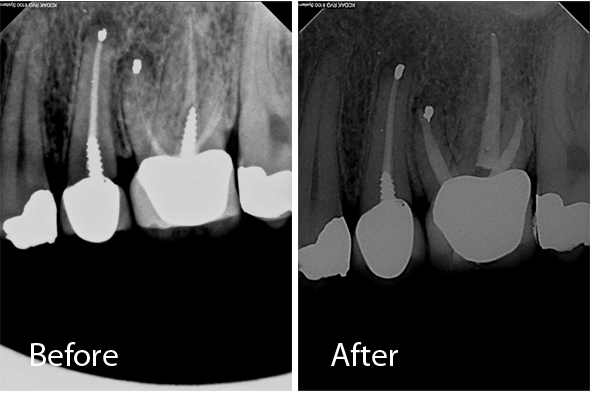

These X-ray images demonstrate the quality and precision of Dr. Portugeys' endodontic procedures. Click any image to view it larger.

Root Canal Premolar – 3 Canals

Retreatment Premolar

Root Canal Molar

Retreatment Molar

Retreatment Molar / Post Removal